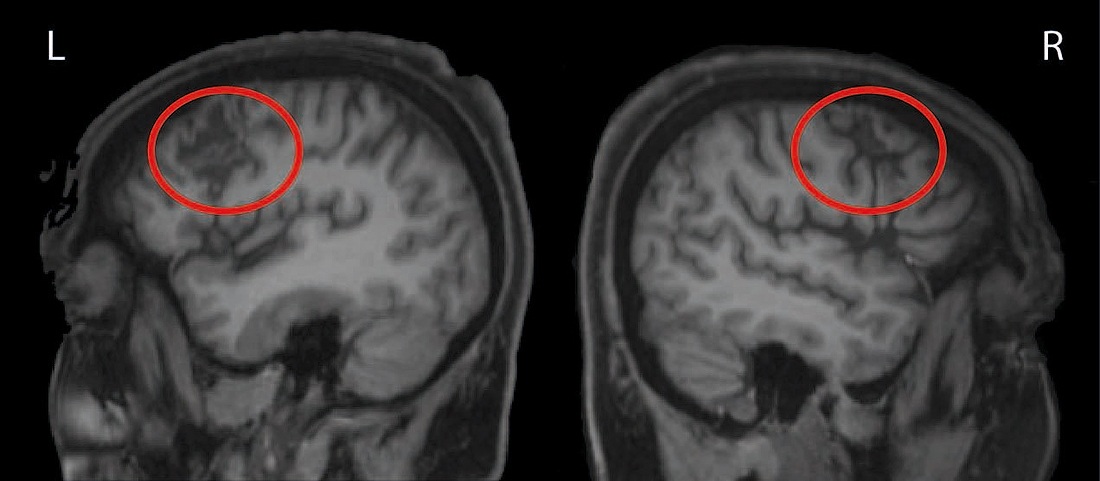

Изображение мозна на МРТ

Анатомическое изображение мозга пациента, записанное с помощью магнитно-резонансной томографии. Красные кружки указывают на поражения с обеих сторон мозга, вызванные ударами (L — левое полушарие; R — правое полушарие)

Особенность случая пациентки заключалась в том, что повреждения ограничились только нижними участками пересечения и проявлялись в обоих полушариях мозга равномерно (как на картинке). Обычно инсульт повреждает большие участки и не ограничивается описанной областью. Кроме того, он редко наносит вред участкам, гомологичным друг другу с обеих сторон. Ситуация для пациентки очень сложная, но ученым этот случай предоставил уникальную возможность проанализировать роль пострадавших участков в обеспечении исполнительных функций.